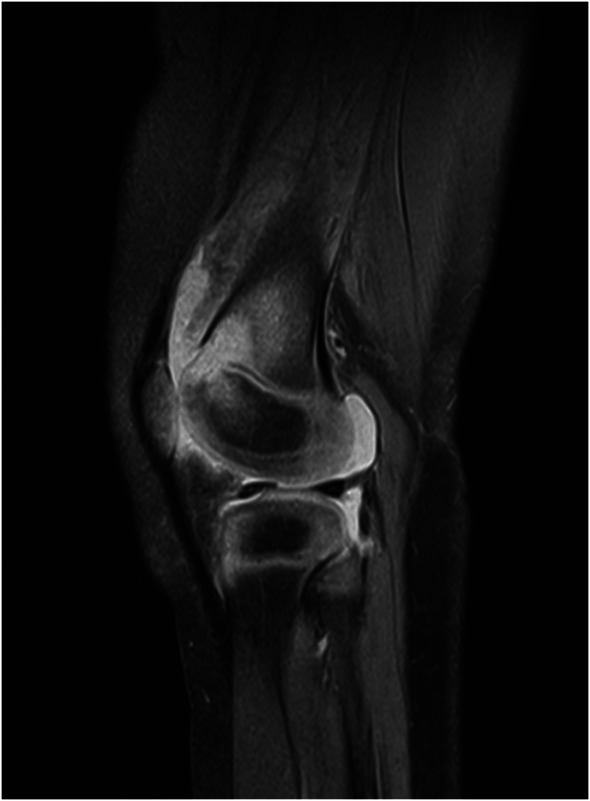

Abstract Image